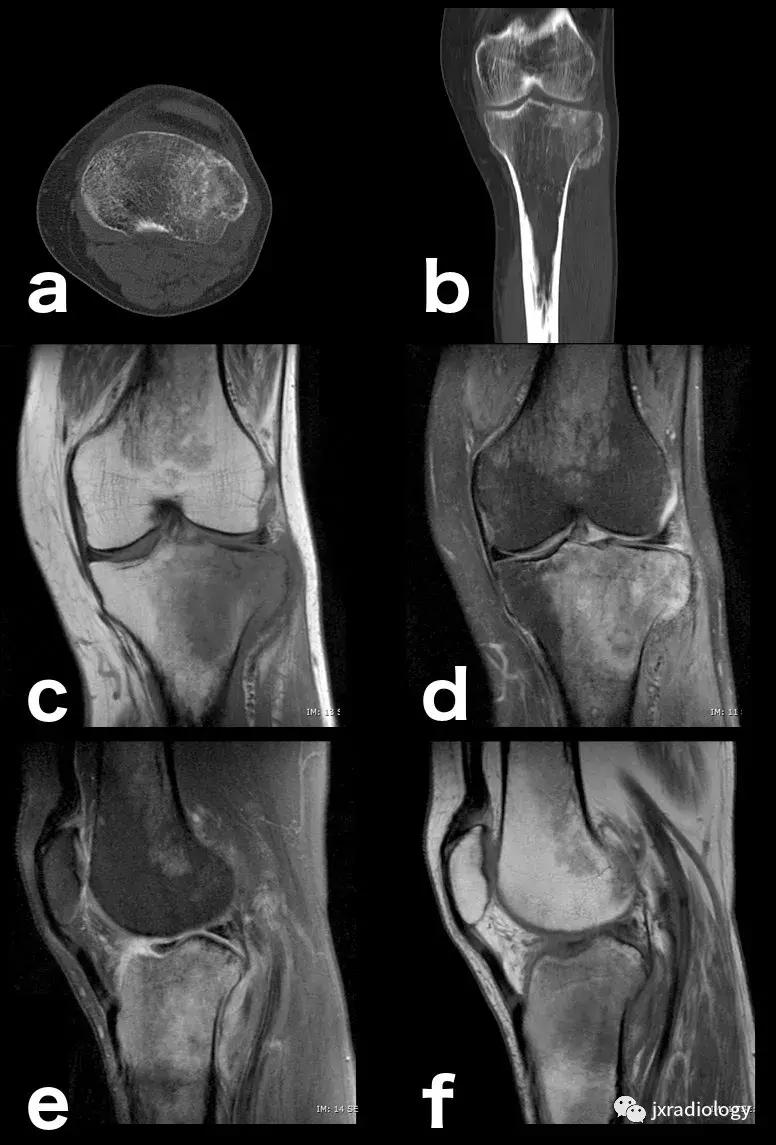

图14:创伤性骨水肿,肉眼可见的亚急性骨折:即使CT扫描(a,b)上的骨折线稍不明显,MRI上骨髓水肿也指出病变(c,d,e,f)。